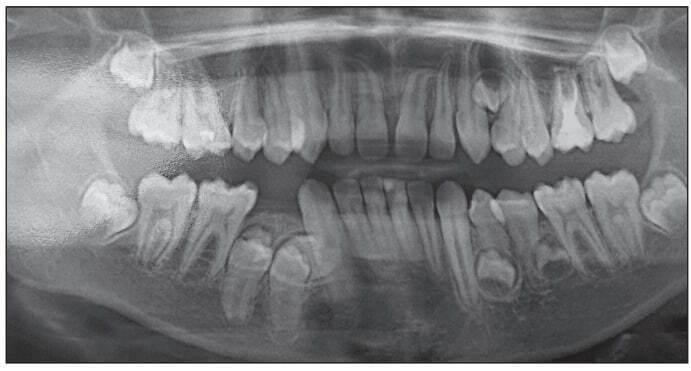

Выявлены зачатки 1.1, 2.1, 2.4, 3.4, 3.5, 4.4, 4.5, корни которых находятся в стадии апексогенеза. Количество сверхкомплектных зубов на ортопантомограмме точно определить не удалось. Наклон ретенированных постоянных зубов был разнообразным. Конвергенция зубов, ограничивающих дефекты зубных дуг, и дефицит места в дуге препятствовали прорезыванию ретенированных зубов в дугу. По результатам клинических и рентгенологических методов исследования сформулирован диагноз «дистальная окклюзия, глубокая резцовая дизокклюзия; сужение и укорочение зубных дуг, тесное положение зубов; ретенция 1.1, 2.1, 2.4, 3.4, 3.5, 4.4, 4.5 зубов; ретенция сверхкомплектных зубов». Комплексный план лечения включал ортодонтические и хирургические вмешательства. Ортодонтическое лечение было начато с создания места в зубной дуге для прорезывания ретенированных центральных резцов верхней челюсти при помощи небной пластинки с расширяющим винтом и искусственными резцами. Хирургическое вмешательство включало удаление сверхкомплектных зубов в области 1.1, 2.1 зубов. Через шесть месяцев началось прорезы вание 1.1 и 2.1 зубов. В этой связи искусственные резцы были сошлифованы, съемный аппарат оставлен для сохранения места в зубной дуге для прорезывания резцов. Для оценки эффективности результатов проведенного лечения и уточнения плана лечебных мероприятий пациент был повторно направлен на ортопантомографию (рис. 3), для уточнения ситуации – на компьютерную томографию челюстей, по результатам которой выявлены пять сверхкомплектных зубов, в том числе в области верхних клыка и первого премоляра слева – один, нижних премоляров слева – два, нижних премоляра справа – два.

Рис. 3. Ортопантомограмма Ф. А., 11 лет, на этапе лечения

Изучено положение сверхкомплектных зубов, локализующихся в области верхушки альвеолярного гребня с язычной стороны 4.4 и 4.5 зубов. Оказалось, что мезиальный сверхкомплектный зуб расположен горизонтально в направлении зубной дуги, а бугры дистального направлены в язычную сторону. Признаки патологии костной ткани не обнаружены (рис. 4).